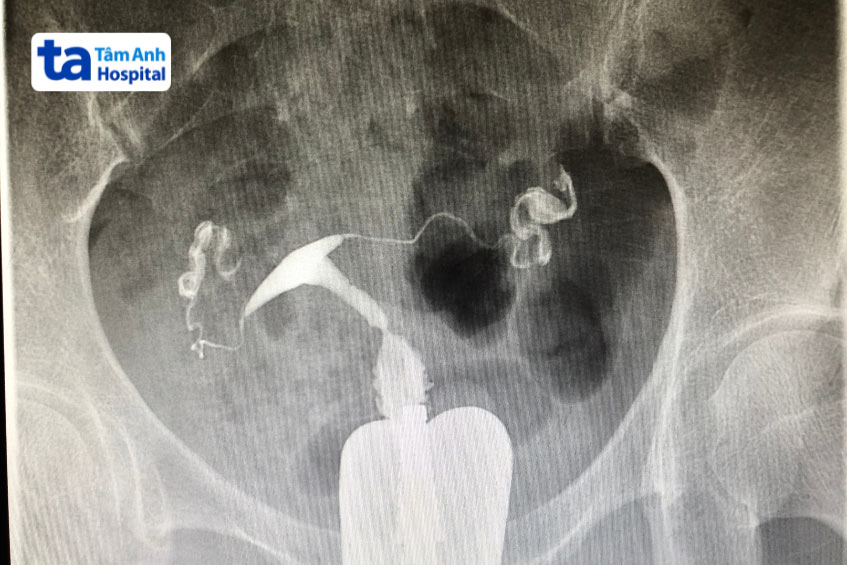

Chụp tử cung vòi trứng nhằm khảo sát, đánh giá tình trạng buồng tử cung và 2 vòi tử cung để xem có yếu tố nào gây bất lợi cho quá trình điều trị IVF hay không. Điều này nhằm tối đa cơ hội điều trị IVF thành công ở vợ chồng hiếm muộn. Kết quả chụp tử cung vòi trứng giúp đánh giá cấu trúc buồng tử cung và tình trạng lưu thông vòi tử cung. Nếu phát hiện bất thường ở các bộ phận này, bác sĩ sẽ có những khảo sát và phương án xử trí phù hợp.

Kết quả chụp tử cung vòi trứng là một trong những cơ sở để bác sĩ đánh giá khả năng sinh sản của người phụ nữ và khả năng ảnh hưởng đến kết cục điều trị IVF. Chụp tử cung vòi trứng giúp chẩn đoán một số bệnh lý: